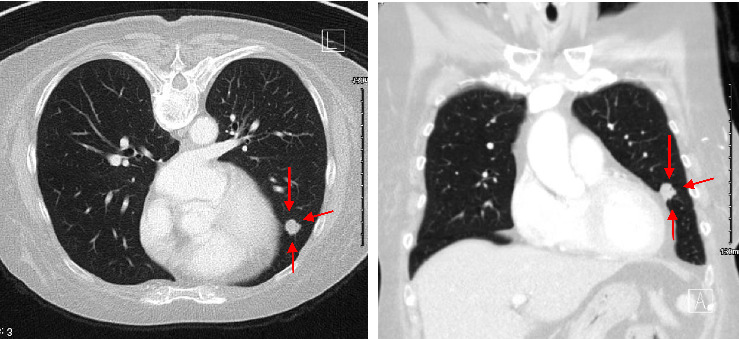

结直肠癌转移到十二指肠是非常罕见的,并提出了重大的诊断和治疗挑战。我们描述了一位68岁的女性右结肠腺癌患者,尽管接受了FOLFOX化疗,但仍发生了十二指肠转移。向FOLFIRI的过渡取得了有限的成功,强调了创新方法的必要性。遗传分析显示KRAS G12D突变,针对该突变的靶向治疗尚未获批。免疫组织化学证实十二指肠肿块起源于胃肠道。文献表明,手术切除可以提供治疗潜力,在某些情况下,虽然它是不可行的。新兴的kras靶向药物,如MRTX1133,代表了解决这种突变的有希望的选择。该病例强调了管理罕见转移模式的挑战,个性化治疗的潜力,以及进一步研究晚期结直肠癌创新治疗的必要性。它强调了制定有针对性的策略来改善这种复杂转移性疾病患者预后的重要性。

Metastasis to the duodenum from colorectal cancer is exceptionally rare and presents significant diagnostic and therapeutic challenges. We describe a 68-year-old female with right colon adenocarcinoma, who developed a duodenal metastasis despite treatment with FOLFOX chemotherapy. Transition to FOLFIRI yielded limited success, emphasizing the need for innovative approaches. Genetic analysis revealed a KRAS G12D mutation, for which targeted therapies are not yet approved. Immunohistochemistry confirmed the gastrointestinal origin of the duodenal mass. Literature indicates that surgical resection can offer curative potential in select cases, although it was not viable here. Emerging KRAS-targeted agents, such as MRTX1133, represent promising options for addressing this mutation. This case underscores the challenges of managing rare metastatic patterns, the potential of personalized therapies, and the necessity for further research into innovative treatments for advanced colorectal cancer. It highlights the importance of developing targeted strategies to improve outcomes for patients with such complex metastatic diseases.